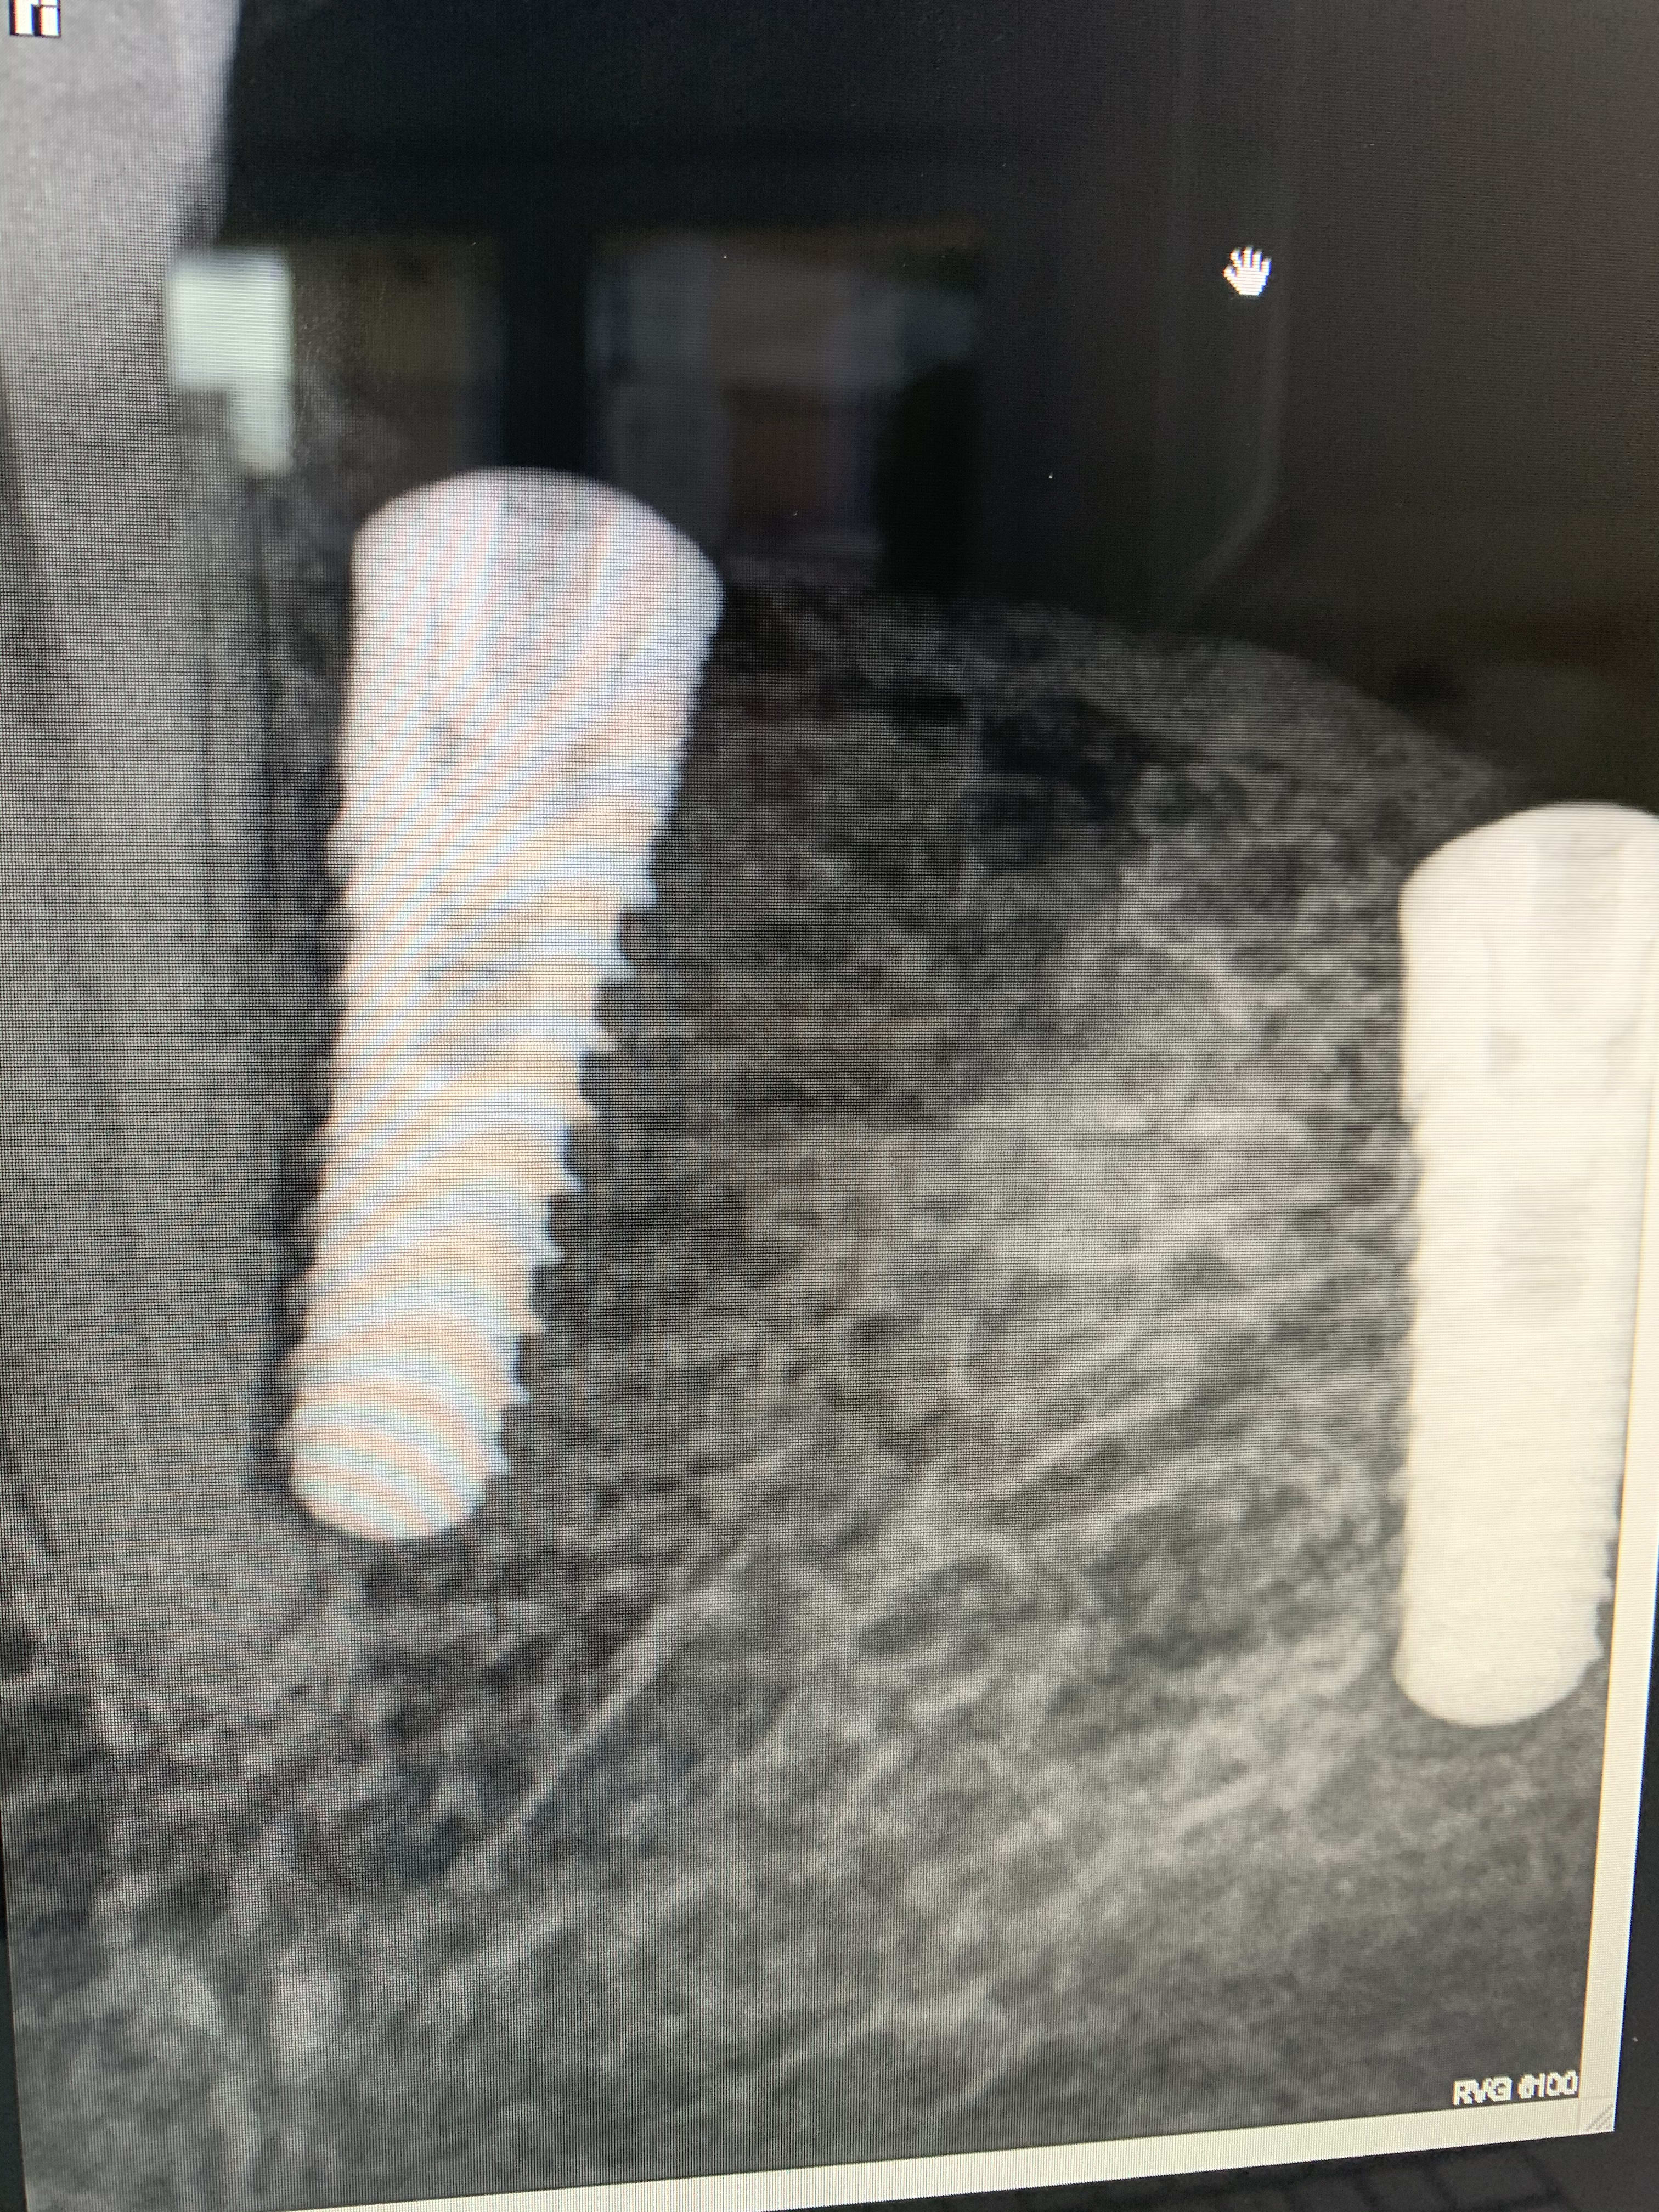

J’ai posé deux implants 34 36 l’autre jour pour futur bridge. J’ai utilisé le wam guide pour évaluer mes distances et mes axes

Je posé mes implants en faisant attention à chaque étape, à la fin, je visse meme 2 transferts pour vérifier le parallélisme et l’axe d’occlusion. Tout est parfait. Le col de mon implant en 34 est bien à distance de ma Canine, L’axe est bien parallèle, je suis content je suture. Je prends une rétro alvéolaire et là je vois ça ! Certes la rétro alvéolaire accentue le fait que l’implant est proche, On a même l’impression que le col est quasi collé alors que ce n’est absolument pas le cas en bouche ! mais là, j’ai tapé dans la canine.

Quelle est la conduite à tenir ? Dois-je déposer ? Dans combien de temps puis-je reposer ? Quel est le risque pour la canine ?

Scan pour vérifier! Si on pose en lingual (donc décalé) dans une partie courbée de la mandibule et si on prend une radio, on peut avoir ce genre d’image stressante . Sans toucher aucunement la dent voisine .

tu peux avoir une image comme çà car ton axe implantaire peut ne pas être identique à celui de la dent naturelle dans le sens vestibulo/lingual et avec la radiographie tu peux avoir une déformation géométrique en plus (film un peu plié ou axe du tube plus mésio/distal)